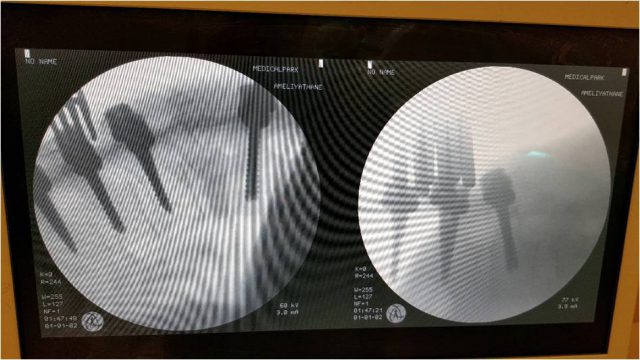

Bel kayması ameliyatları yaklaşık 2-2,5 saat sürmekte, hasta ameliyattan yirmi dört saat sonra ayağa kalkıp kişisel ihtiyaçlarını yardım olmaksızın yapabilir durumda olur. Hastanede iki gün yatması yeterlidir. Bel omurgasına kaymayı önlemek amacıyla titanyum vidalar konmaktadır. Bu vidalar ömür boyu hastada kalmaktadır. Ameliyatta cilt dikişi konmamaktadır. Gelişen yeni teknolojilerle, tecrübeli bir cerrahın elinde felç olma sakat kalma riski yoktur.

Bel kayması, yani bizi taşıyan omurga kemik sisteminin birbiri üzerinde kayıp omuriliği sıkıştırması, oldukça sık görülen bir rahatsızlıktır. Yürürken sık sık durma isteği bacaklarda uyuşma, yanma hissi ortaya çıkan bu rahatsızlık tedavi edilmezse idrar tutamama, erkeklerde cinsel yetersizlik, yürüyememe, belden aşağısını hissetmeme gibi sonuçlara da yol açabilir. Bel kaymasının tek tedavisi beli titanyum vidalarla sabit hale getirip kaymasını önlemektir. Halk arasında “platin” ya da “vida” ameliyatı olarak adlandırılan bu tedavi yöntemi halk arasında oldukça riskli olarak bilinmektedir. Bu nedenle, bu ameliyatı olması gerekenler bu tedaviden kaçmakta ömür boyu kalitesiz bir yaşam sürmektedirler. Oysa tecrübeli bir cerrahın ellerinde bu ameliyatlar sıfır riskle tamamlanmaktadır. Yeni teknolojilerle tüm bu endişeler ortadan kalkmakta, bilgisayar desteği ile vidalar tam yerine konabilmektedir. Bu sistem sayesinde bel kayması ameliyatları sorunsuz olarak uygulanabilmektedir. Önemli olan doğru zamanda doğru teşhisi koymaktır.